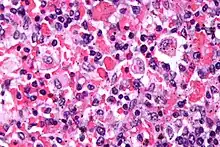

| Micrograph showing red blood cells within macrophages. H&E stain. | |